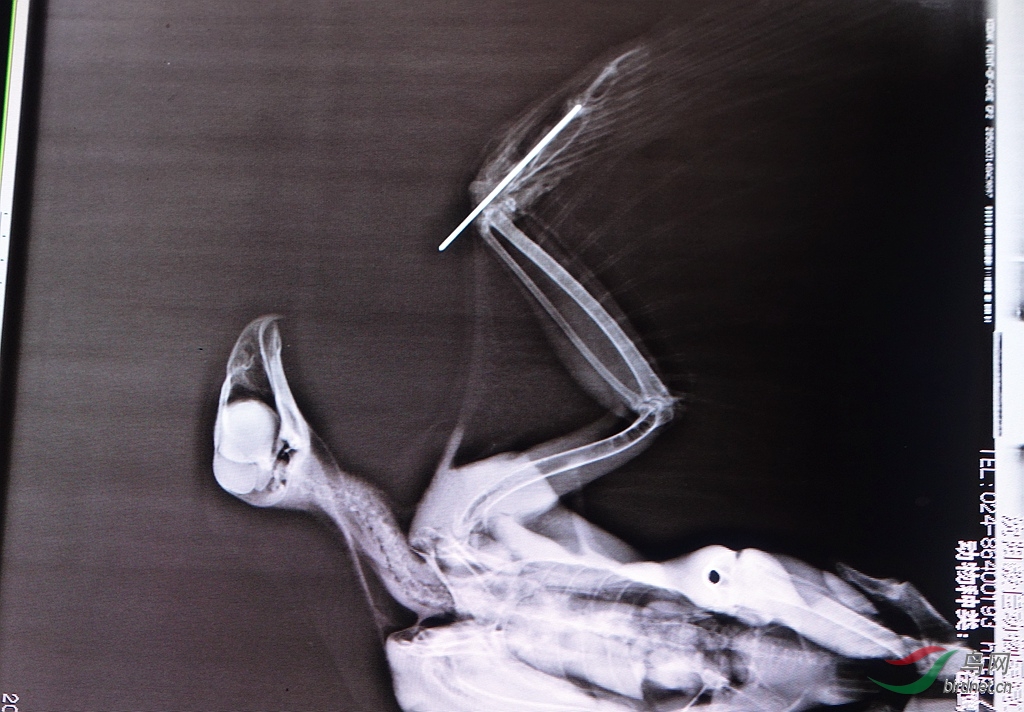

[救助] 2013年沈阳护鸟志愿者救助日记 |